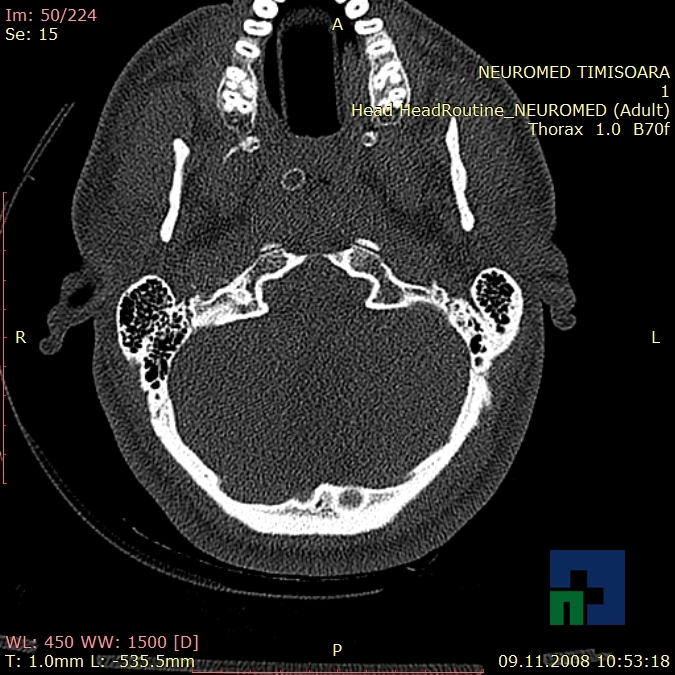

Examinare de rutină cerebrală, nativ și cu substanță de contrast (SDC) pentru diagnosticul:

- Accidentelor vasculare cerebrale ischemice sau hemoragice